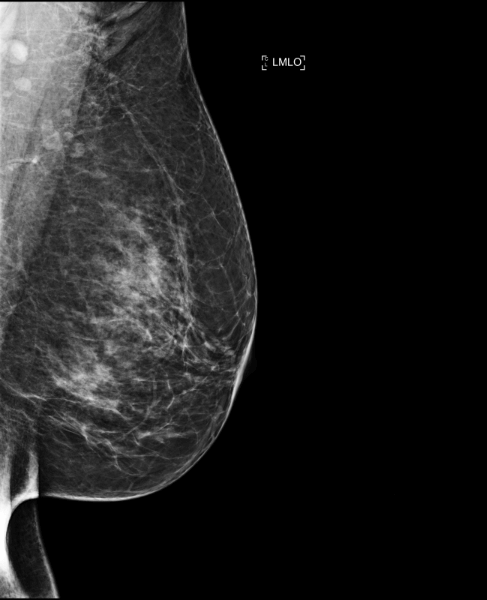

Cas de la semaine (semaine 51, 2024)

Lors d’une mammographie de dépistage, une lésion suspecte sur le sein droit,

invisible sur les images 2D, a été repérée grâce aux coupes de tomosynthèse.

MammoScreen a aussi détecté cette lésion suspecte sur la coupe 14 de la

tomosynthèse, avec un score de 9, ce qui confirme son caractère suspect.

Dans ce cas particulier, la tomosynthèse a joué un rôle crucial en révélant à la fois au

radiologue mais aussi à l’IA une lésion tumorale qui aurait autrement pu passer

inaperçue.